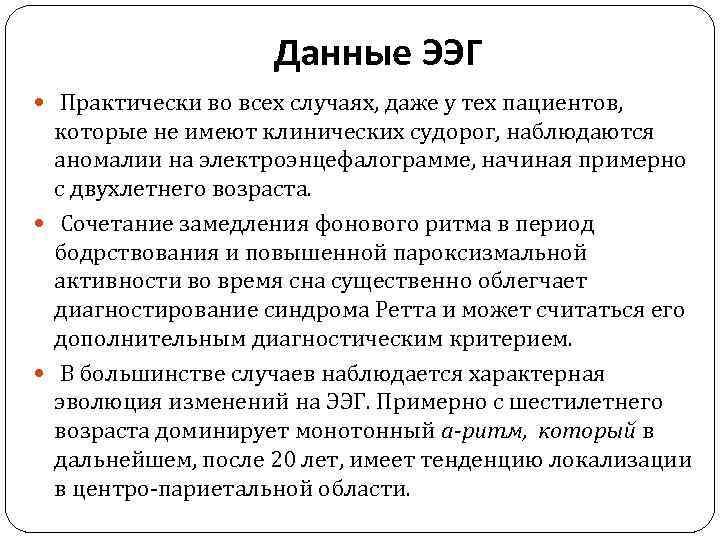

Данные ЭЭГ Практически во всех случаях, даже у тех пациентов, которые не имеют клинических судорог, наблюдаются аномалии на электроэнцефалограмме, начиная примерно с двухлетнего возраста. Сочетание замедления фонового ритма в период бодрствования и повышенной пароксизмальной активности во время сна существенно облегчает диагностирование синдрома Ретта и может считаться его дополнительным диагностическим критерием. В большинстве случаев наблюдается характерная эволюция изменений на ЭЭГ. Примерно с шестилетнего возраста доминирует монотонный а-ритм, который в дальнейшем, после 20 лет, имеет тенденцию локализации в центро-париетальной области.